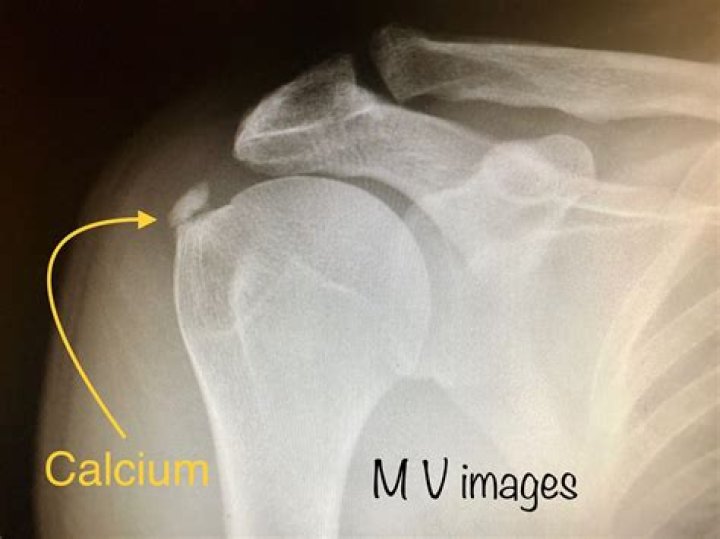

What does calcification of the shoulder mean?

Shoulder calcification occurs when calcium deposits form in a rotator cuff tendon.

What causes calcium in the shoulder?

Can lack of calcium cause shoulder pain?